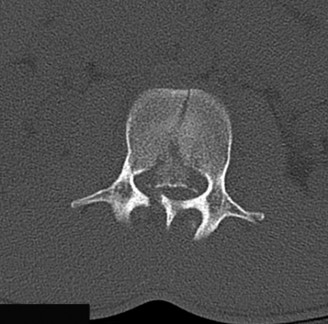

The diagnostic imaging workup for this patient spanned his initial presentation at age 15 and his subsequent return at age 20, providing a textbook illustration of the natural history of untreated isthmic spondylolysis. During his initial visit, standard weight-bearing anteroposterior (AP), lateral, and bilateral oblique radiographs of the lumbar spine were obtained. The lateral radiograph demonstrated a normal lumbar lordosis and preserved L5-S1 disc space height, with no evidence of anterior translation (spondylolisthesis). However, the oblique radiographs revealed the pathognomonic "collar on the Scotty dog" sign. The "Scotty dog" represents the posterior elements of the vertebra, where the nose is the transverse process, the eye is the pedicle, the front leg is the inferior articular process, and the neck is the pars interarticularis. A radiolucent line across the neck confirmed the presence of bilateral L5 pars defects.

To evaluate the neural elements and the soft tissue structures, a comprehensive MRI of the lumbar spine without contrast was obtained. The T2-weighted sagittal and axial sequences confirmed the Grade 2 anterolisthesis and demonstrated severe bilateral foraminal stenosis at L5-S1. The exiting L5 nerve roots were severely compressed between the hypertrophied, fibrocartilaginous pseudarthrosis tissue of the pars defect dorsally, and the bulging, degenerated L5-S1 disc and superior endplate of S1 ventrally. Furthermore, the MRI revealed Modic Type II changes (fatty replacement of the subchondral bone marrow) in the adjacent vertebral endplates, confirming chronic biomechanical stress and discogenic degeneration. The central canal remained relatively patent, which is characteristic of isthmic spondylolisthesis, as the posterior neural arch is left behind during the anterior translation of the vertebral body.